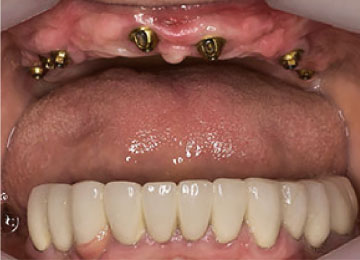

Имплантация зубов: фото «До» и «После»

Фото ДО

Фото ПОСЛЕ

Наведите для просмотра

All-on-4